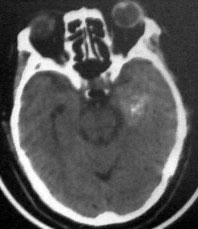

病人男性52岁,一年前曾患脑出血.今突发剧烈头痛,恶心,呕吐..病人家属说病人自去年脑出血以后,精神异常!请大家看看左侧颞叶病灶考虑什么?片子不是很清楚请大家见谅!!左颞叶病灶ct值最高处为85hu

左侧颞叶海马回钩部斑片状高密度致密影,考虑:出血.

病人此次症状应与右侧丘脑及基底节出血破溃入脑室有关。

左颞叶病灶我认为不是出血,就算是出血,也与右侧病灶性质不同。理由:1.该病灶密度较淡而不均匀,其间见斑点状更高密度。急性出血,应该不会是这个样子。

2.病灶对周围无推移挤压迹象,也无水肿。倒是病灶旁边、左侧环池局部扩张,与右侧病灶

完全不一样。

综合上诉特点,左颞叶病灶我首先考虑:avm。

左侧颞叶考虑血管畸形,右侧丘脑及基底节出血破溃入脑室